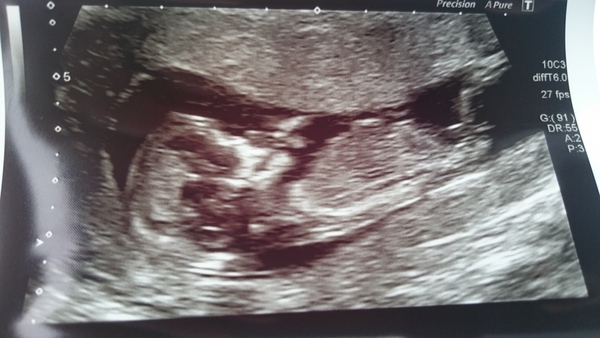

OK ladies after a long wait and busy day here is our little bean sucking its thumb Grin

12weeks 5 day's for picture! But all OK Grin